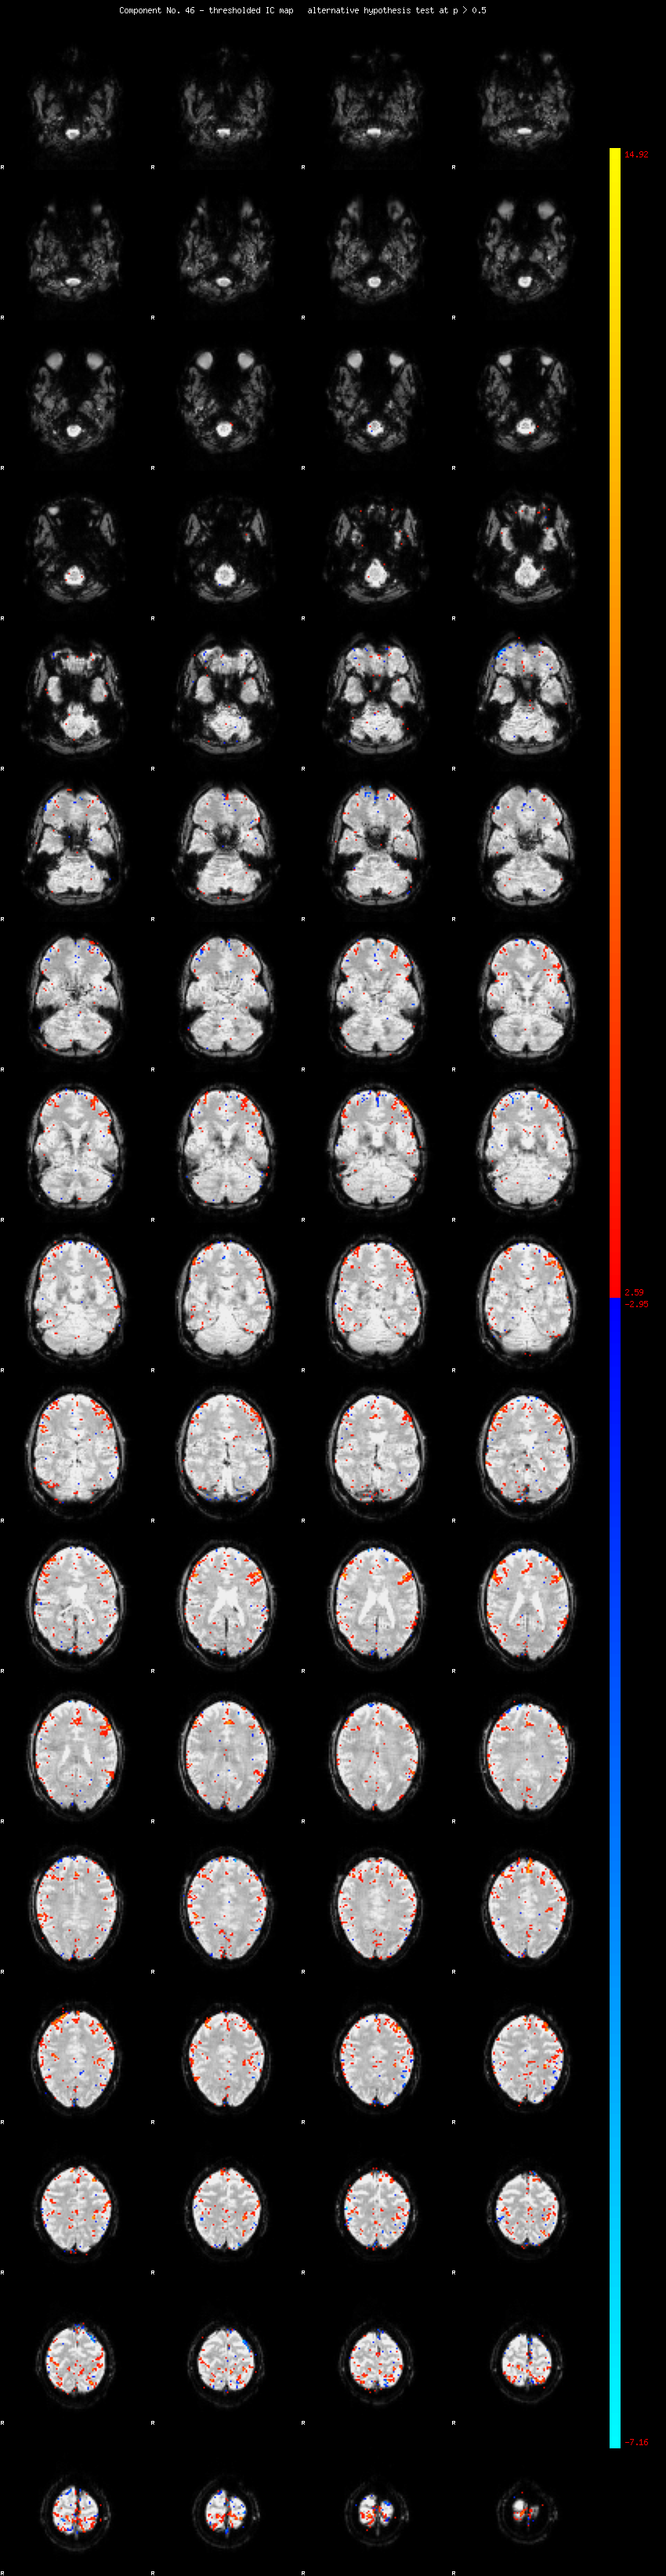

MELODIC Component 46

1.03 % of explained variance;     0.68 % of total variance